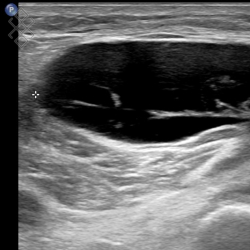

Échographie du Genou

La durée de l'examen est d'environ 20 minutes. Il est indolore et est réalisé par un médecin radiologue.